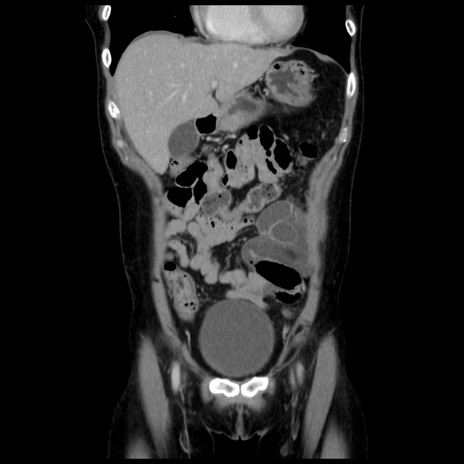

症例10(冠状断像)

【症例】 50歳代女性

【主訴】 腹痛

【現病歴】前日生レバーを食べた。今朝に排便あり。 昼前に突然発症の腹痛を生じ、当院救急外来を受診した。

【既往歴】 子宮筋腫にてで子宮全摘後

【身体所見】 意識清明、腹部:平坦、軟、下腹部やや左を中心に圧痛・反跳痛あり、筋性防御あり

【データ】WBC 7800、CRP 0.07